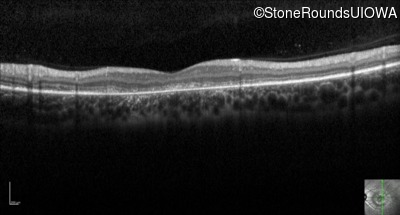

Optical Coherence Tomography - Right - 20/200 -3

Exemplar / OCT Stack

OCT Stack